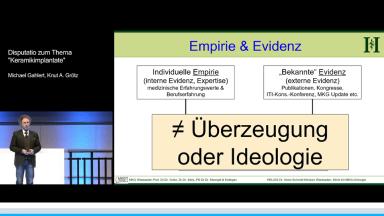

Die vorliegenden Präsentationen von zwei sehr erfahrenen Rednern geben einen aktuellen Überblick zum Thema «Keramik- im Vergleich zu Titanimplantaten». Dabei werden vor allem klinische Langzeiterfahrungen mit Keramikimplantaten aus Zirkonoxid vermittelt, und es wird dargestellt, dass sich seit Markteinführung die konstante Weiterentwicklung signifikant auf die Verlässlichkeit dieser Implantate ausgewirkt hat. Darüber hinaus wird diskutiert, ob durch metallische Stoffe klinisch relevante Nachteile für Patienten entstehen können und ob ein metallfreies Leben und Arbeiten überhaupt sinnvoll ist. Die Darstellung «pro Keramik» und «pro Titan» erfolgt dabei nicht nur durch emotionale und empirische Argumente, sondern die inhaltlichen Kernpunkte werden mit Evidenz-basierten Daten belegt.